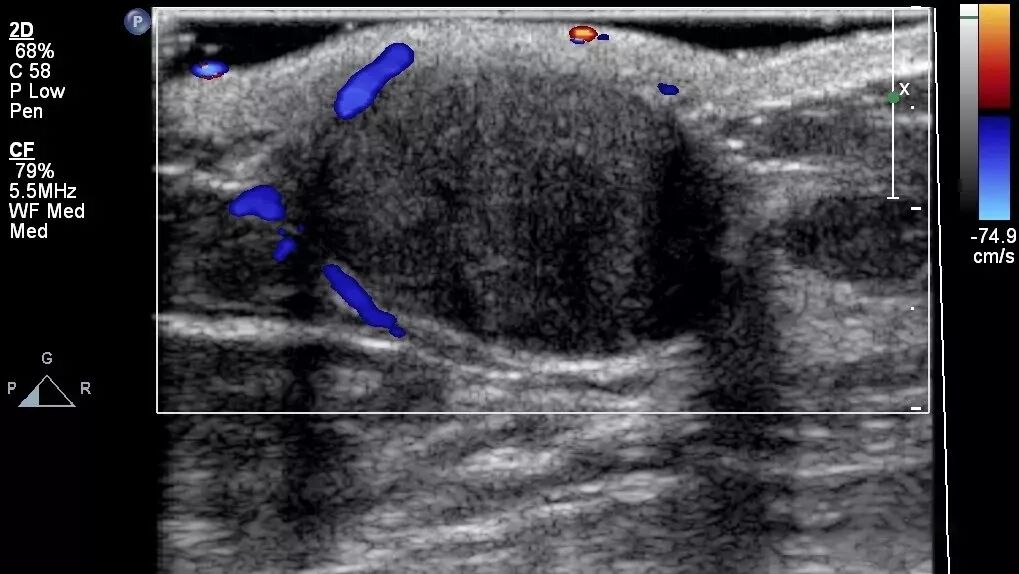

镜面伪像

声束斜射到声阻差很大的膈-肺界面时发生全反射而产生镜面伪像,这时膈下的为实像,膈下为虚像。

声像图上的虚像总是位于实像的深方。

图为肝脏内血管瘤的声像图,深方为血管瘤位于膈上的镜面伪像。